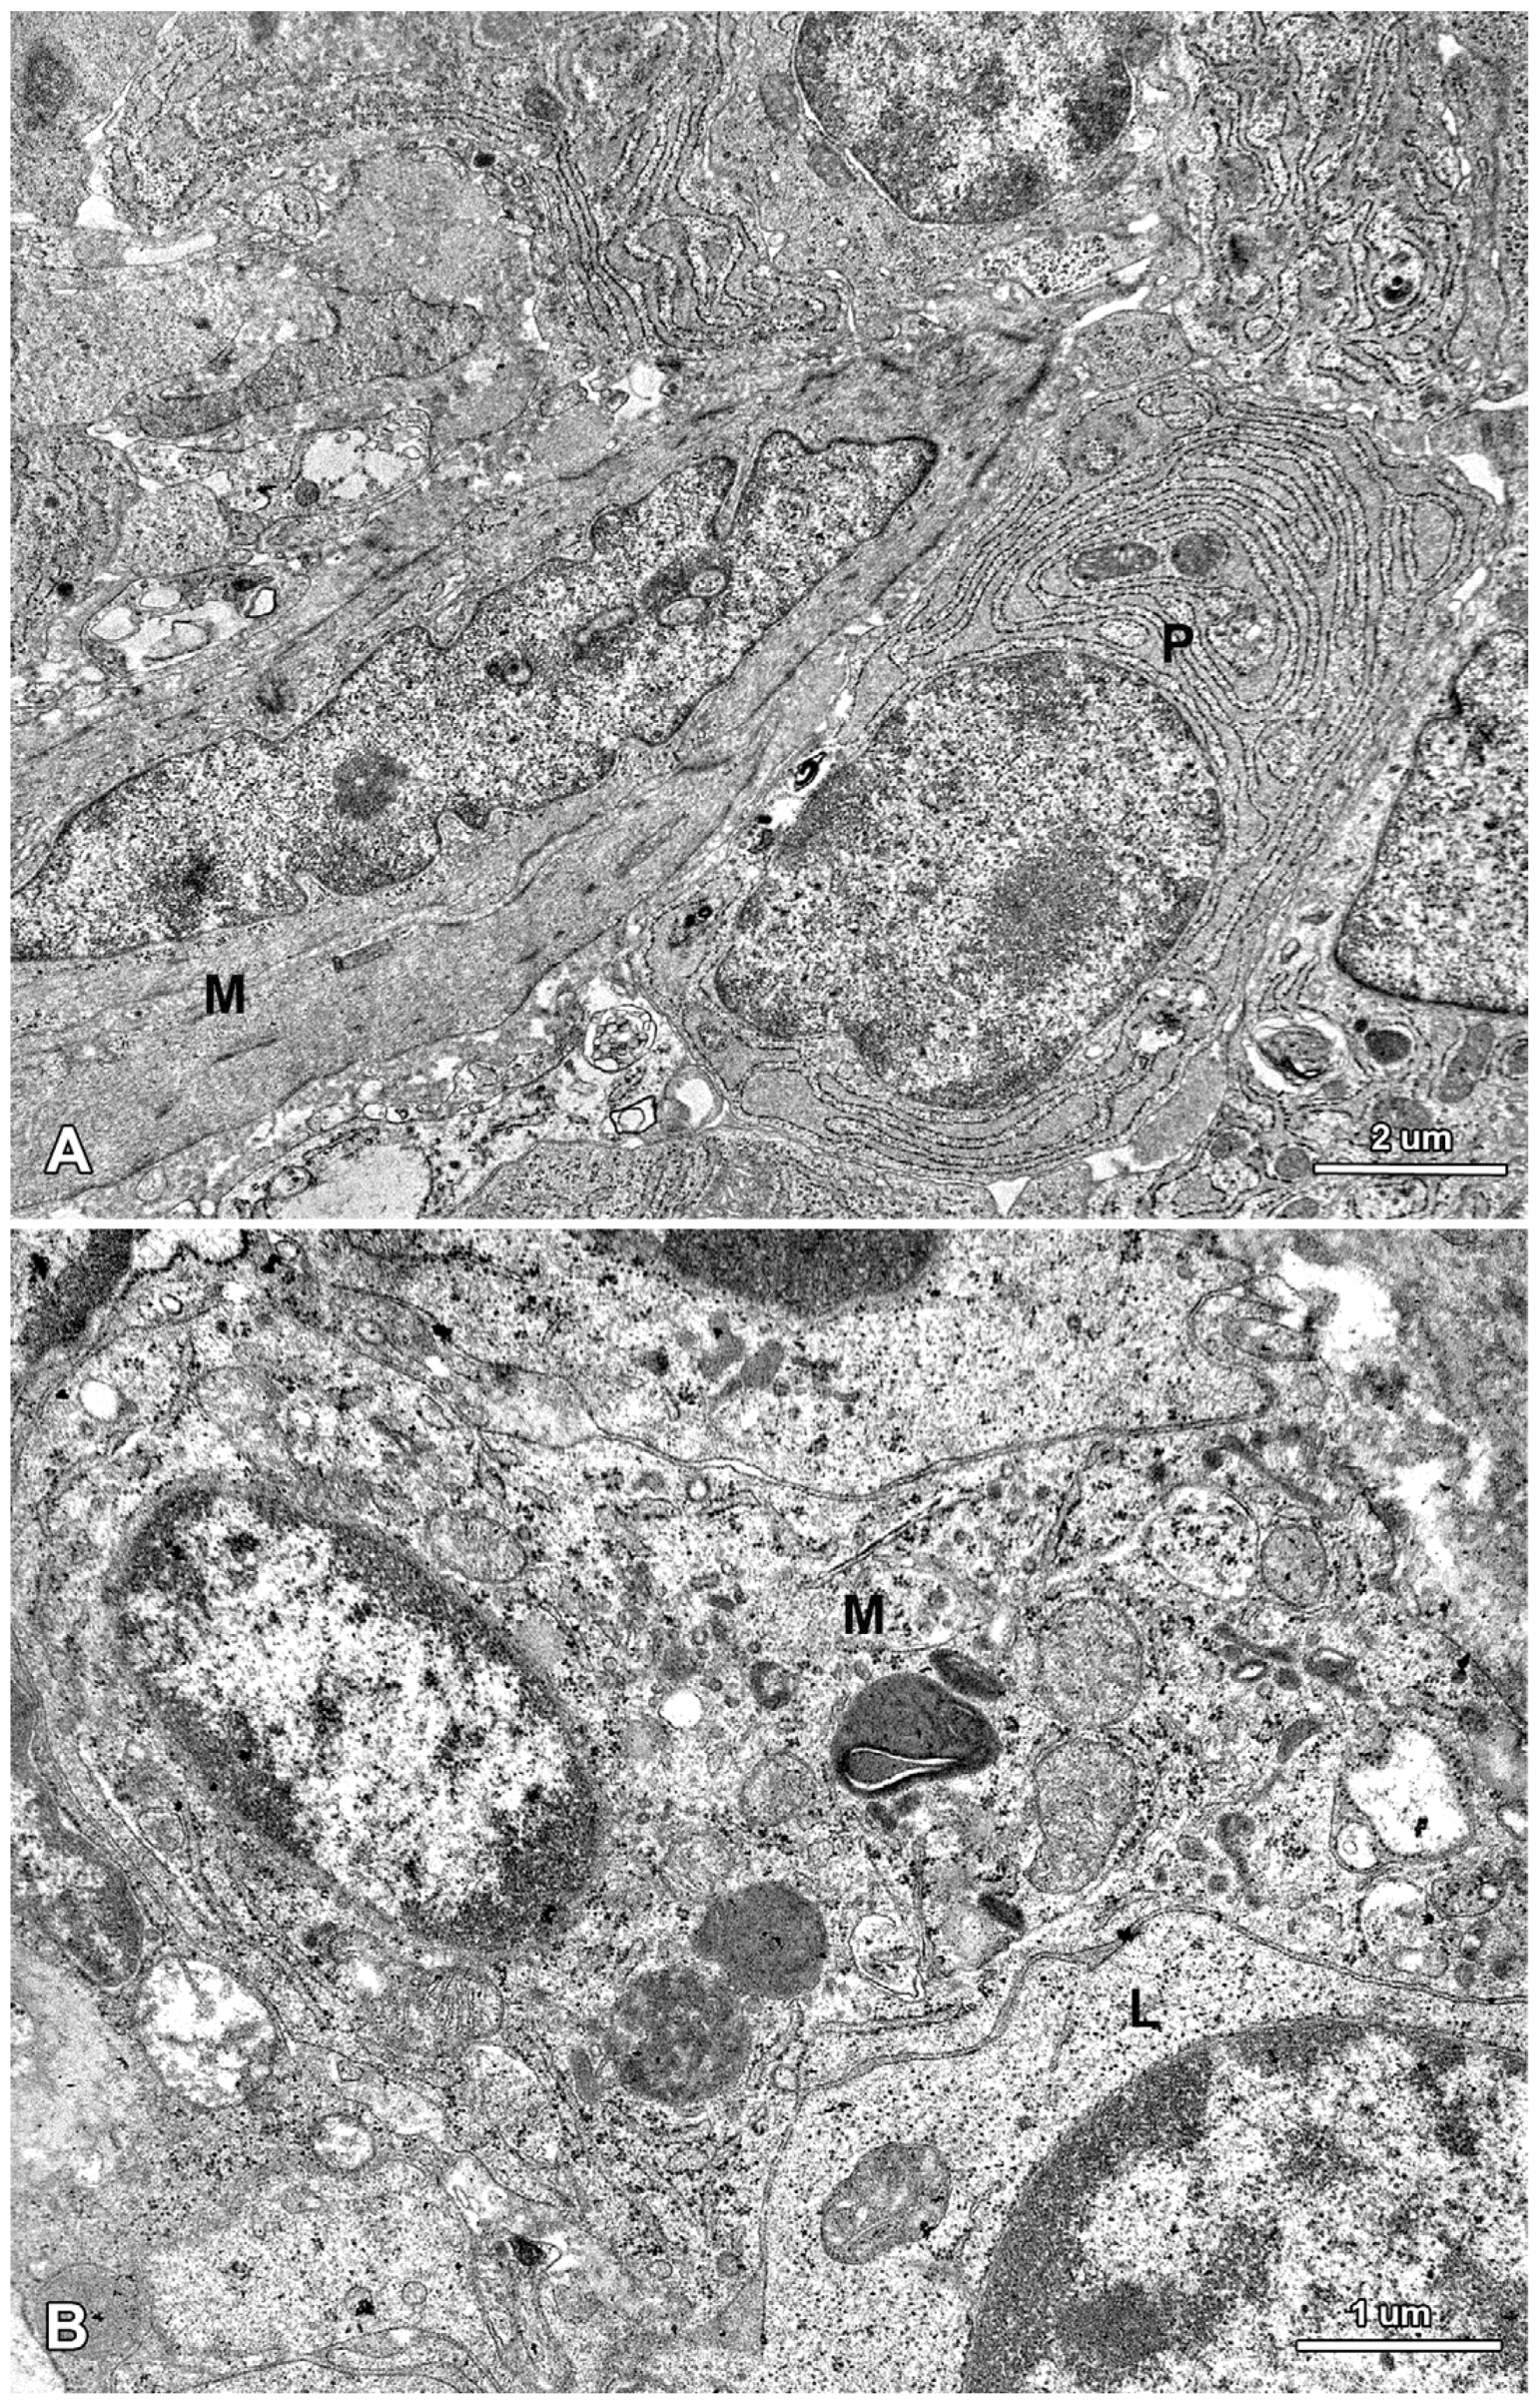

The lamina propria of the jejunum of pigs treated with mycotoxins was formed by a loose connective tissue with numerous cells: fibrocytes and fibroblasts, lymphocytes, plasma cells, mast cells, eosinophils, and macrophages (Figure 10). Myocytes were observed inside of the villi (Figure 10). The difference between the groups was due to plasma cells, which were more numerous in the lamina propria of gilts treated with ZEN or DON for one, three, and six weeks than in the control pigs.

Figure 10.

Ultrastructure of the jejunal mucosa lamina propria in a pig that received DON for six weeks. (A) Plasma cells (P) and myocyte (M) in the villus; (B) Macrophage (M) and lymphocyte (L) in the stroma between the intestinal crypts.